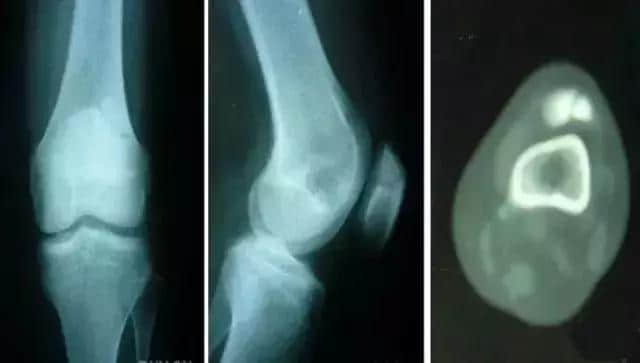

5 分裂 (二分)髌骨

常见于儿童,多双侧性。 一般认为是正常骨化的变异,可在十几岁时融合。症状:运动时疼痛或运动后疼痛,膝关节屈曲时疼痛、下跪时疼痛,上下楼梯时疼痛,行走时疼痛,受冷时疼痛。

分裂部扣击痛:可诱发有症状的分裂髌骨的疼痛,无症状者阴性。分裂骨片局部骨性隆起。 股四头肌萎缩, 髌骨摩擦音,大多无关节积液、跛行和关节活动度受限。有时需与骨折鉴别。